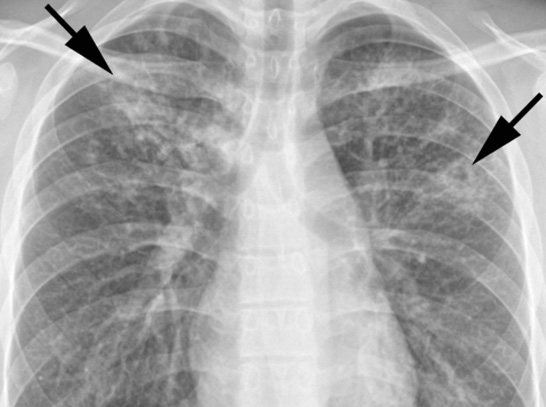

Diagnosis of active TB relies on radiology(commonly chest X-rays), as well as microscopic examination and microbiological culture of body fluids. Diagnosis of latent TB relies on the tuberculin skin test (TST) and/or blood tests. Treatment is difficult and requires administration of multiple antibiotics over a long period of time. Social contacts are also screened and treated if necessary. Antibiotic resistance is a growing problem in multiple drug-resistant tuberculosis (MDR-TB) infections. Prevention relies on screening programs and vaccination with the bacillus Calmette–Guérin vaccine

If a tuberculosis infection does become active, it most commonly involves the lungs (in about 90% of cases). Symptoms may include chest painand a prolonged cough producing sputum. About 25% of people may not have any symptoms (i.e. they remain "asymptomatic"). Occasionally, people may cough up blood in small amounts, and in very rare cases, the infection may erode into the pulmonary artery, resulting in massive bleeding (Rasmussen's aneurysm). Tuberculosis may become a chronic illness and cause extensive scarring in the upper lobes of the lungs. The upper lung lobes are more frequently affected by tuberculosis than the lower ones. The reason for this difference is not entirely clear. It may be due either to better air flow, or to poor lymph drainage within the upper lungs.